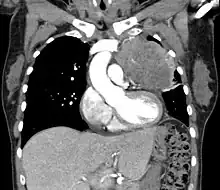

Thymic carcinoma

Thymic carcinoma seen on CT.

Diagnosis of thymic carcinoma is based on a combination of clinical, radiologic, and biopsy findings. Most early cases are asymptomatic and found incidentally on chest radiographs as a mass in the anterior mediastinum. Further evaluation consists of additional imaging, such as CT, MRI, and PET, and tumor biopsy, which is the gold standard and provides the definitive diagnosis.[5] Biopsy may be done prior to surgery by fine needle aspiration or during the surgery with concomitant evaluation by the pathologist.[8] Other carcinomas with malignant spread to the thymus are on the differential diagnosis and must be excluded, as they may appear similar to thymic carcinoma on histopathological examination. [3]